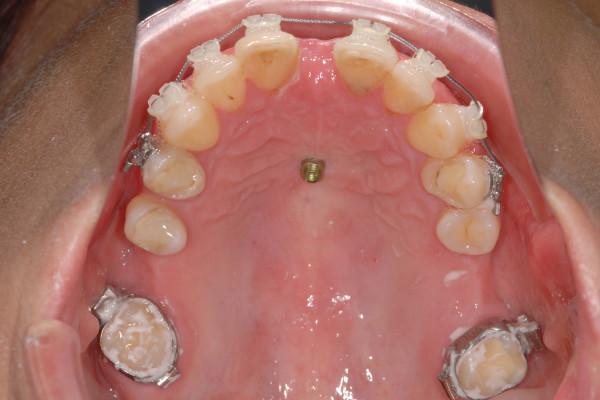

A sample of 20 consecutively treated patients (15.6 ± 7.2 years) was examined. A long mini-implant with a length of 11 mm and a diameter of 2 mm was inserted into the anterior palate of each patient. Resonance frequency analysis (RFA) was performed after insertion (T0), two weeks (T1), four weeks (T2), and six weeks (T3). Insertion depth (ID) and the maximum insertion torque (IT) were measured. RFA, ID and IT data were tested for correlations. RFA values were tested for statistical differences between the different times. Data was compared to a matched control group of patients who received short mini-implants with a length of 9 mm and a diameter of 2 mm.

对 20 例连续治疗的患者(15.6±7.2 岁)进行了检查。每位患者的前腭均植入 1 枚长 11mm、直径 2mm 的迷你种植体。植入后即刻(T0)、2 周(T1)、4 周(T2)和 6 周(T3)时进行共振频率分析(RFA)。测量植入深度(ID)和最大植入扭矩(IT)。对 RFA、ID 和 IT 数据进行相关性检验。对不同时间的 RFA 值进行统计学差异检验。将 RFA 值与接受长 9mm、直径 2mm 的短迷你种植体的匹配对照组进行比较。